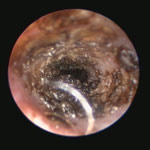

耳ダニ感染後の鼓膜喪失と中耳炎

長く耳ダニに気付かず治療が遅れた猫です。すでに鼓膜を失っており、中耳をきれいに洗浄すると赤い肉芽が確認できました。この肉芽を除去し点耳薬で治療すると改善。鼓膜が全く残っていないため鼓膜の再生は期待できませんが、痛みや痒みもなく元気に過ごしています。